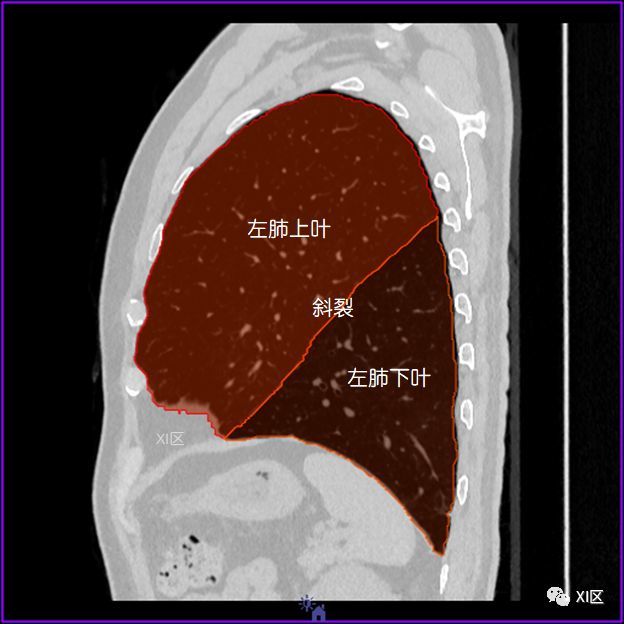

如此详细的肺部影像解剖有点儿酷

完美标注肺部横断面解剖肺门肺段及血管解剖